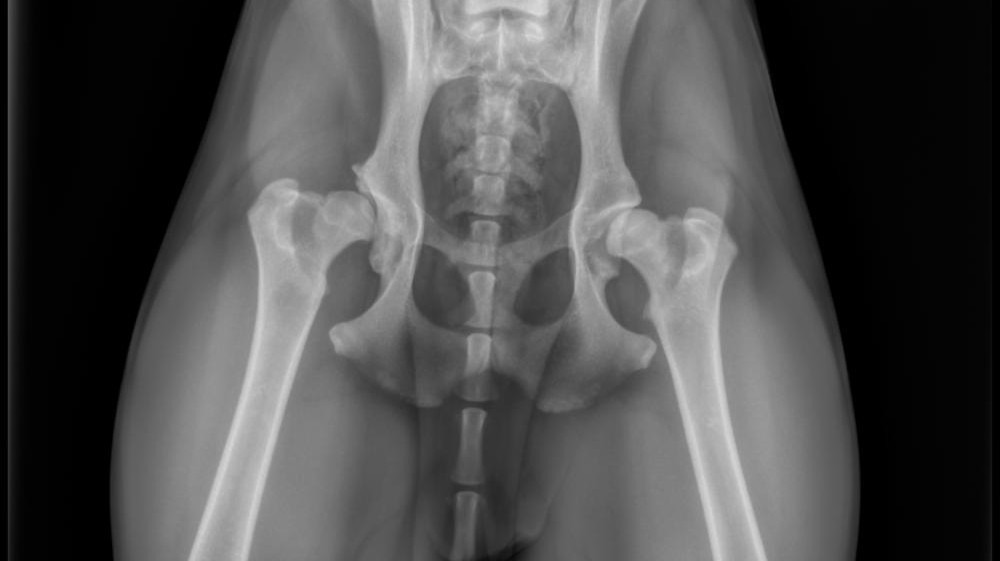

In December her foster noticed Kashka limping after playing and brought her to the vet, where she was diagnosed with severe hip dysplasia. In the months since her diagnosis, the pain on her left side has increased and has significantly limited her ability to do the activities she loves the most: running, playing, and simply enjoying life the way a young dog should. While we are currently managing her discomfort with medication, her hip joint needs surgical repair and physical therapy to allow her to regain a normal quality of life.